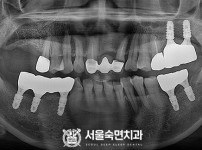

임플란트-전후사진2

치과를-선택할-때-꼭-확인하세요-서울숙면치과-임플란트-전후사진